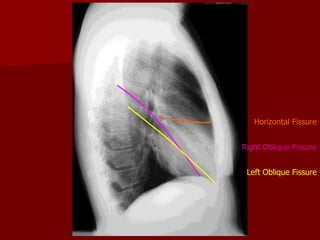

Pulmonary Fissures

Pulmonary fissures are formed with visceral

pulmonary pleura.

RIGHT LUNG

MAJOR FISSURE

OBLIQUE FISSURE

MINOR FISSURE

HORIZONTAL FISSURE

LEFT LUNG

Oblique fissure more clearly seen on Lateral view from

T4-T5 vertebrae to reach the diaphragm and 5 cm

behind the costophrenic angle on left And just behind

the angle on right.

Horizontal fissure more clearly Seen on P.A view

extending from Right hilum to 6th rib in the axillary line

Right Oblique Fissure

Left Oblique Fissure